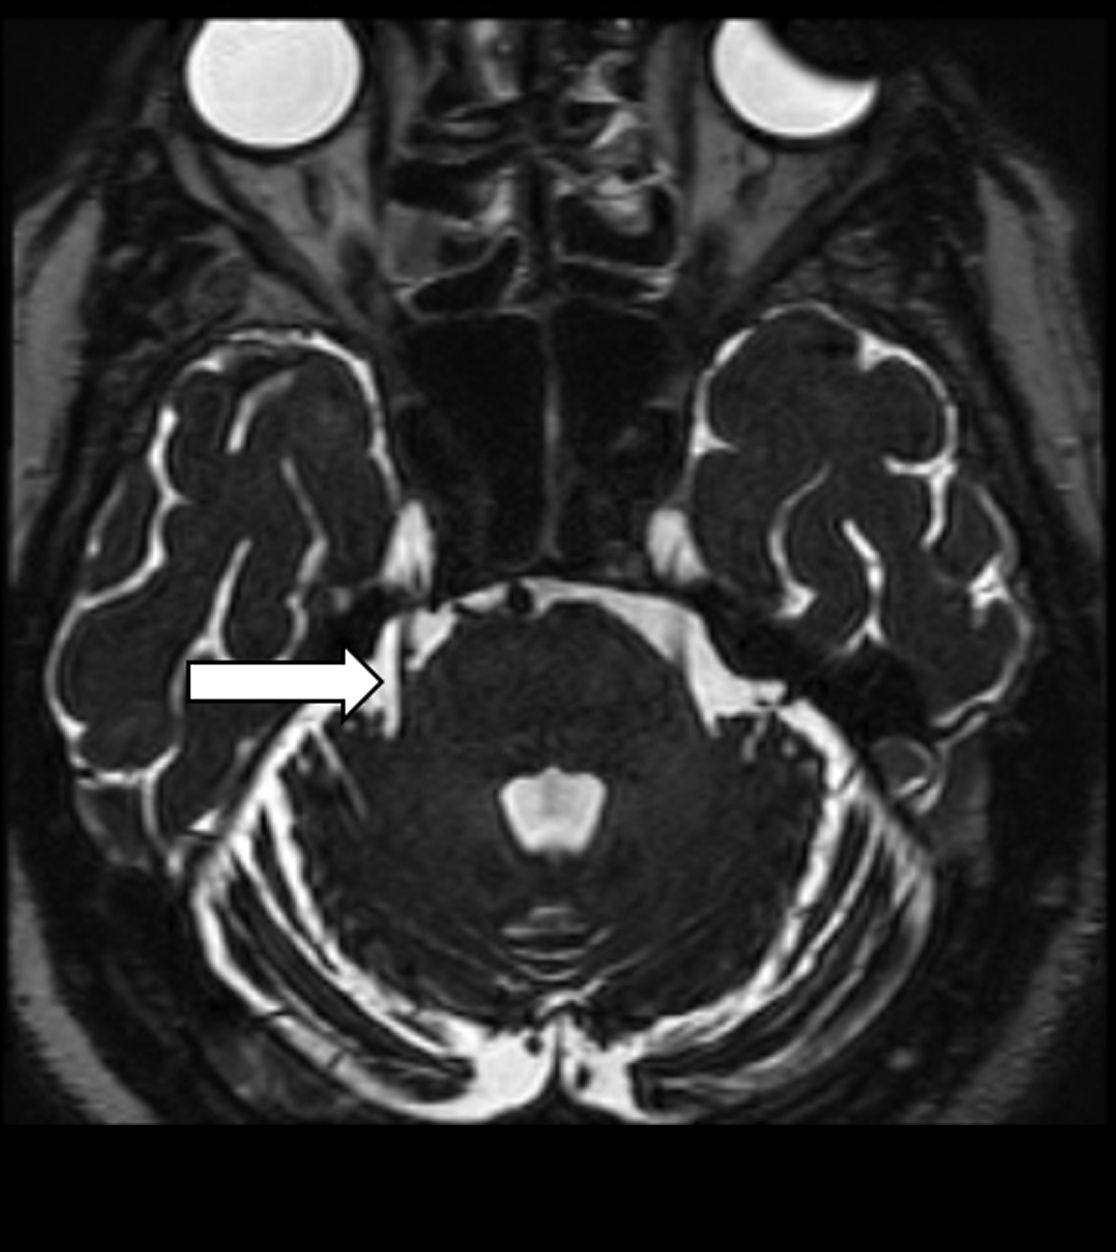

Im Nervenwasserraum (Liquor) einliegender Schlauch zur intrathekalen Therapie (Pfeil)

Liegt bei einer Trigeminusneuralgie eine Gefäßschlinge vor, welche den Trigeminusnerv berührt, kann bei unzureichender Linderung durch eine medikamentöse Therapie ggf. durch eine operative Lösung von Nerv und Gefäß eine Schmerzreduktion erreicht werden. Hierfür wird der Trigeminusnerv an seiner Eintrittsstelle zum Hirnstamm aufgesucht und durch z.B. ein Teflon-Stück vom Gefäß getrennt.

Gefäß-Nerven-Kontakt im Bereich des Nervus trigeminus (Pfeil)

Status nach mikrovaskulärer Dekompression über einen Zugang hinter dem Ohr (Pfeil)